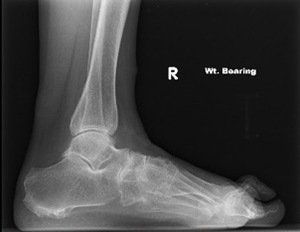

Rheumatoid arthritis is an auto-immune systemic condition that can involve multiple joints in the body. A high percentage of people with rheumatoid arthritis develop symptoms related to their foot or ankle. Symptoms normally commence in the small bones and joints of the toes and forefoot. They can then progress to the joints in the back of the foot known as the rearfoot and ankle. There are other forms of inflammatory arthritis that affect the foot and ankle including gout, ankylosing spondylitis and psoriatic arthritis. Patients with these conditions are almost always under the care of a Rheumatologist who is a specialist of joint disease.

The exact cause of rheumatoid arthritis is unknown however there are several theories including a genetic predisposition and a chemical or environmental trigger to activate the disease. As an auto-immune condition, the body’s defence system turns on itself and produces substances that attack and inflame its own joints. With 25% of the body’s total bones being located in the foot and ankle, it makes sense this condition is commonly encountered in the foot and ankle.